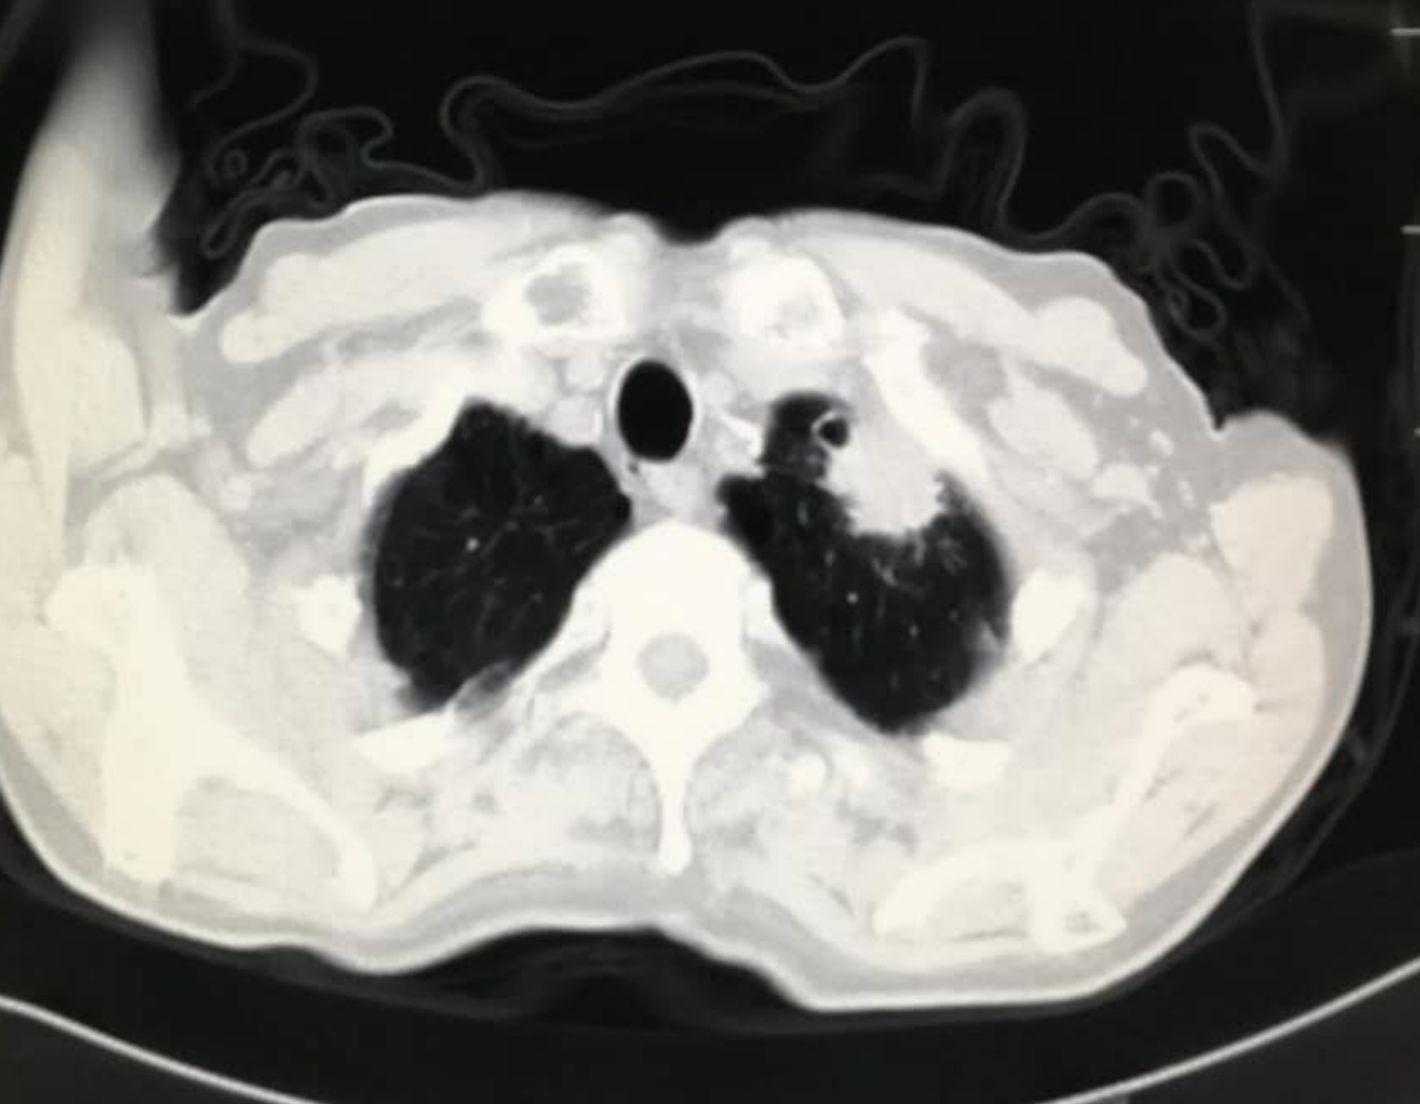

肺癌的病理类型细分下来有太多种,比如鳞癌、腺癌、肉瘤样癌、神经内分泌癌等,每一种类型又有很多病理亚型,其进展速度也并不一致。比如有的肺腺癌,可以在相当长的时期内表现为混合磨玻璃密度结节影,随访观察生长缓慢。从预防过渡医疗角度可以先定期随访而不急于手术切除。但是,癌症终究是癌症,它终究会在某一刻显露出阴森森的獠牙,呈现出恶狠狠的爆发式生长!

比如下面这例肺腺癌,随访4年增长缓慢:

但是到了第5年,突然加速:

这个时候就不能排除胸膜侵犯了,手术后的复发率也会相应提高,手术切除难度也加大了。